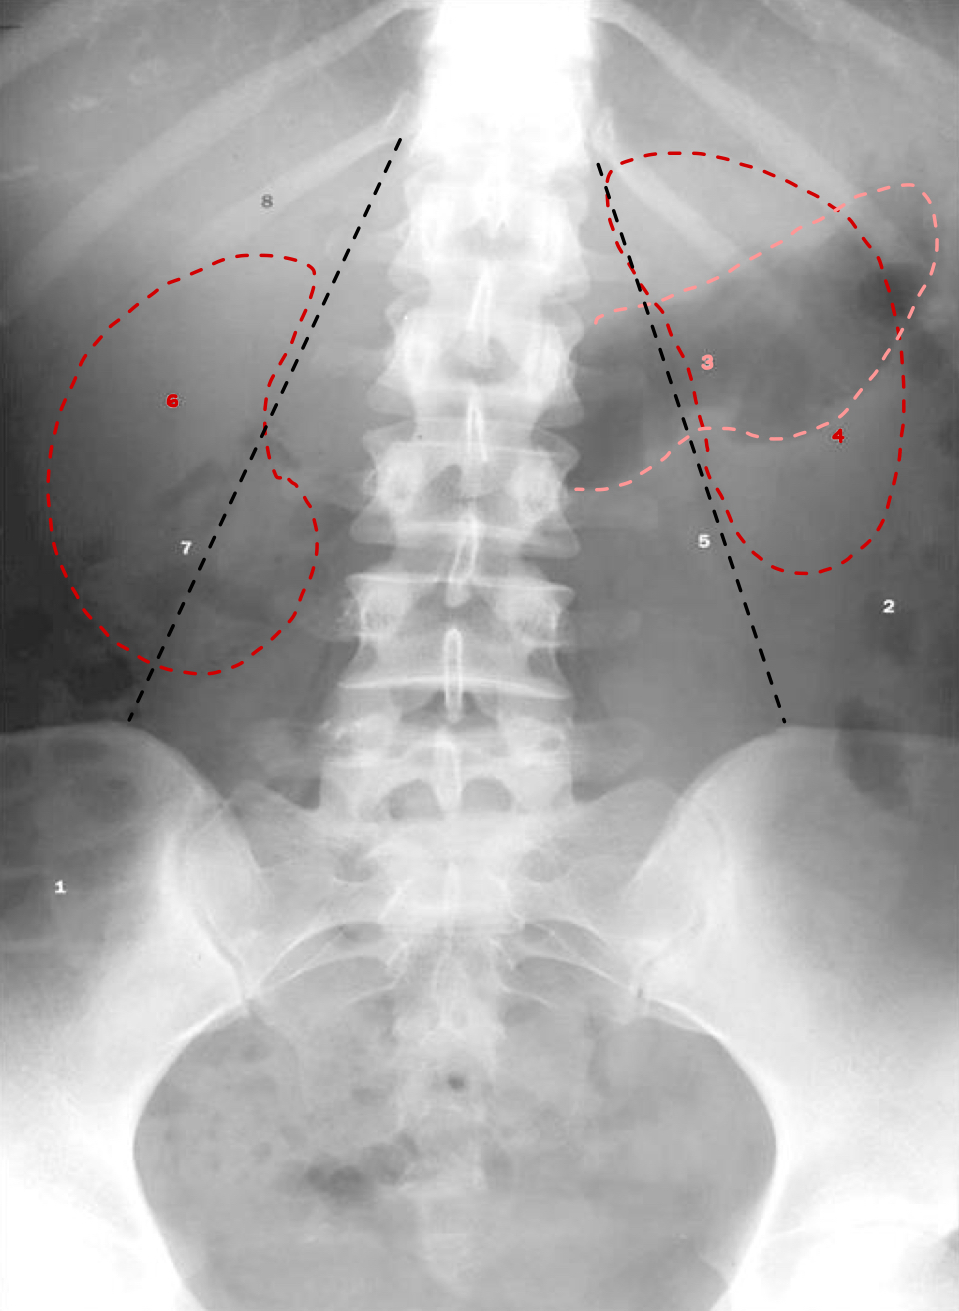

What is 1

ascending colon/large intestine

What is 2

descending colon/large intestine

What is 3

stomach

What is 4

left kidney

What is 5

left psoas muscle

What is 6

right kidney

What is 7

right psoas muscle

What is 8

area of the liver

(number is on 12th floating rib)